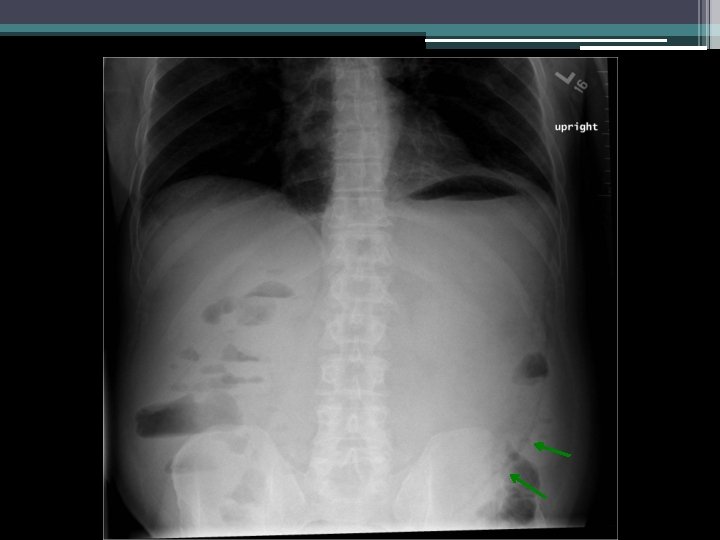

Imaging

Clinical course • • Return of nausea and vomiting NG tube decompression: >3 L nonbloody output Saline load test markedly positive Repeat KUB

Gastric emphysema • Diagnosis: gastric emphysema due to gastric outlet obstruction • Pneumatosis intestinalis ▫ Gastric pneumatosis Gastric emphysema Emphysematous gastritis ▫ Pneumatosis coli